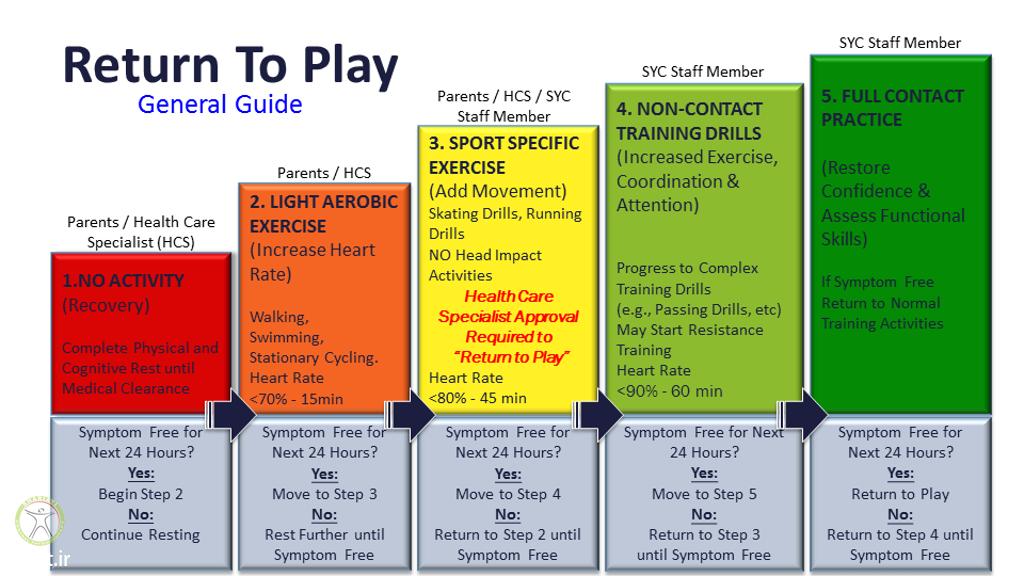

بهبودی کامل آسیب شکستگی دنده حداقل به 8 هفته زمان نیاز دارد برای شکستگی هایی که در آن دنده جابجا شده است بسته به واکنش بدن ورزشکار که توسط ایکس ری مشخص می شود زمان بهبودی طولانی تر خواهد شد و بازگشت به ورزش بر این اساس برنامه ریزی می شود برخی ورزشکاران برای بهبود کامل و بازگشت به فعالیت به سه ماه استراحت نیاز دارند.

ورزشکارانی که در رشته های پر برخورد فعالیت دارند و دنده بر اثر شکستگی جابجا شده یا در سمت شکسته درد قابل ملاحظه ای دارند باید در ادامه فصل مسابقات از جلیقه محافظ استفاده کنند. ورزشکاران رشته های بدون برخورد معمولا به محافظ و بریس نیاز ندارند مگر اینکه در ناحیه شکستگی درد داشته یا دچار مشکل تنفسی شود. ورزشکارانی که تحت درمان قرار گرفته و بهبود یافته اند باید تحت تمرینات آمادگی جسمانی قرار بگیرند تا ظرفیت های قلبی و تنفسی آنها پیش از بازگشت به بازی بهبود یابد.